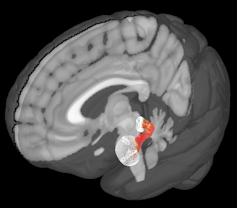

There are two major regions in what brain scientists call the “offspring care neural network,” evolutionarily old structures deep in the brain called the amygdala and the periaqueductal gray.

The periaqueductal gray is another small u-shaped structure at the base of the brain. It plays an important role in controlling basic behaviors like the impulse to cuddle a baby or the instinct to avoid predators.

We found some interesting effects while reviewing images captured during this experiment. Most notably, the amygdalas and their periaqueductal gray were more active for kidney donors than people in our control group, with stronger reactions to fearful and distressed stimuli.

What we found suggests that these two regions might be communicating or otherwise working together. We further tested this finding by looking at another aspect of our brain scans that allowed us to analyze how these two regions are connected by nerve cells.

My colleague Katherine O'Connell, a doctoral student, found that there seemed to be greater structural connections between these two regions too. These connections may help nerve impulses travel between them.

But our findings reinforce earlier neuroscience research that found that the amygdala and periaqeuductal gray, and communication between them, play an important role in caring for distressed and vulnerable others across all mammals – including humans.